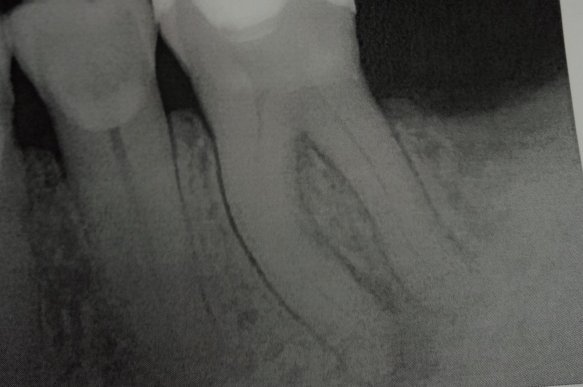

Два года назад опухла десна, зуб начал шататься, врачи сказали, что нужно вырвать зуб, но я не согласился. Потом они сделали надрез и почистили десны от гноя, потом, через несколько месяцев зуб затвердел. Спустя два года начал побаливать по ночам, сегодня сделали рентген, врач говорит нужно вырвать зуб, но мне не хочется.

Возможно в зубе имеется обширный воспалительный процесс, а также воспаление по периодонтальной щели. Данный зуб скорее всего необходимо удалить.